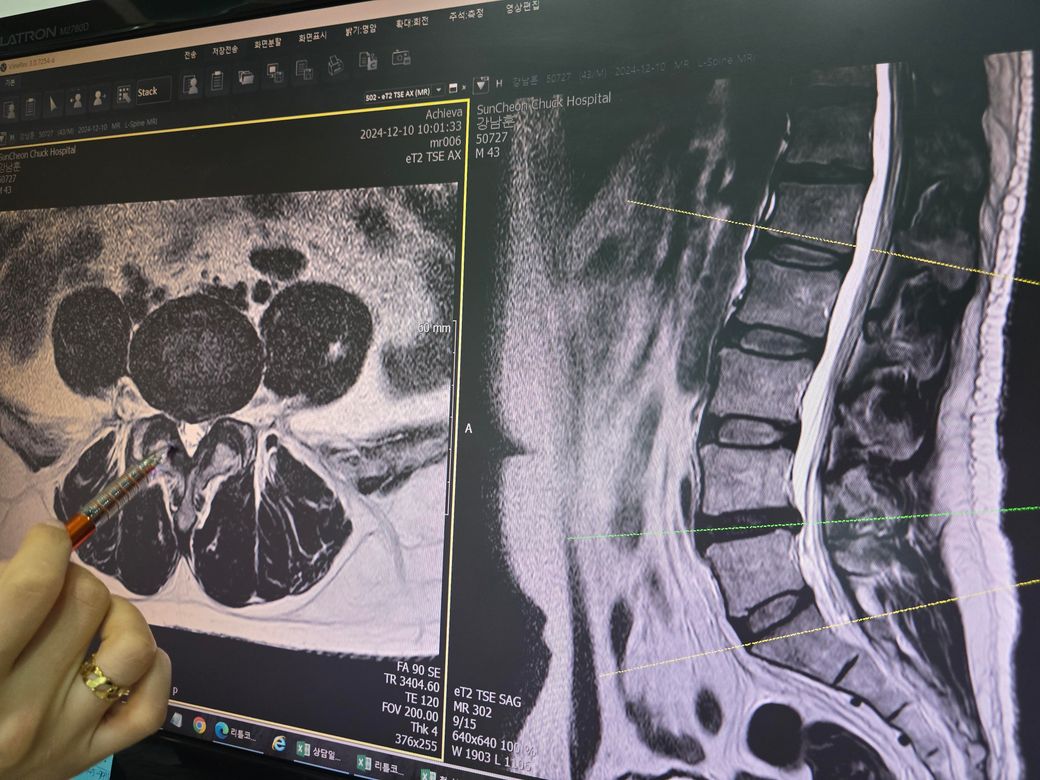

요추4,5 디스크 판정인데 수술을 권유하시는데 그정도로 안좋은 상태일까요?

금일 mri 촬영했는데 시술이나 보존치료가 아닌 단방향내시경수술을 권하시네요

시술단계가 아닌 수술이라는데 그정도일까요?

• 2번 째 사진